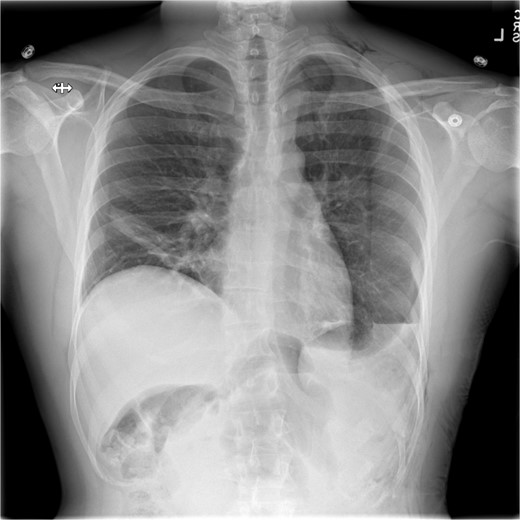

The early postoperative course was unremarkable. The patient reported feeling mild bloating, but was discharged on postoperative Day 1 after removal of a chest tube (Fig. 4). A few hours after discharge from the hospital, he developed dysphagia, progressive abdominal pain, distension, and dyspnea that prompted a return to the hospital. Physical examination revealed tachycardia (132 bpm), mild hypoxia requiring supplemental O2 at 2 L/min via nasal canula, and abdominal distension. Laboratory studies showed WBC of 12 600 cells/μL. A CT scan of the abdomen and pelvis revealed a large, acute organo-axial gastric volvulus without evidence of ischemia, and an intact left hemidiaphragm plication at a similar height to the right hemidiaphragm (Fig. 5). A nasogastric tube was placed with immediate drainage of 1 L of dark bilious fluid with immediate relief of the patient’s symptoms. However, a subsequent film revealed the nasogastric tube projecting toward the upper left chest with presence of colonic haustra (Fig. 6), consistent with acute hemidiaphragm rupture.

Confirmatory abdominal film for nasogastric tube placement demonstrating acute elevation in the left hemidiaphragm, 90-min after the CT, identifying the gastric volvulus.